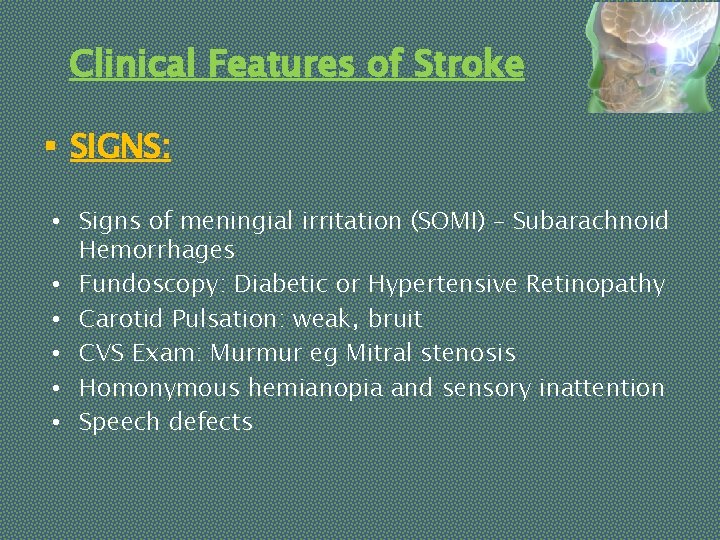

Clinical Features of Stroke § SIGNS: • Signs of meningial irritation (SOMI) – Subarachnoid Hemorrhages • Fundoscopy: Diabetic or Hypertensive Retinopathy • Carotid Pulsation: weak, bruit • CVS Exam: Murmur eg Mitral stenosis • Homonymous hemianopia and sensory inattention • Speech defects